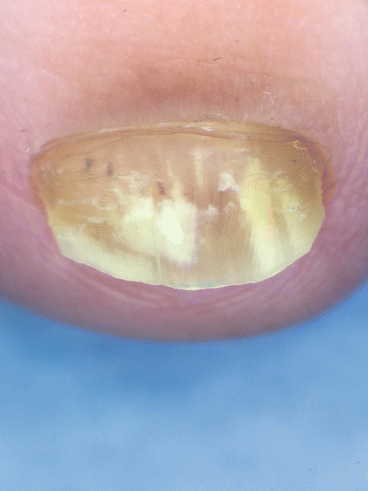

Fig. 4.2

SWO dermoscopy shows that the superficial nail plate is affected